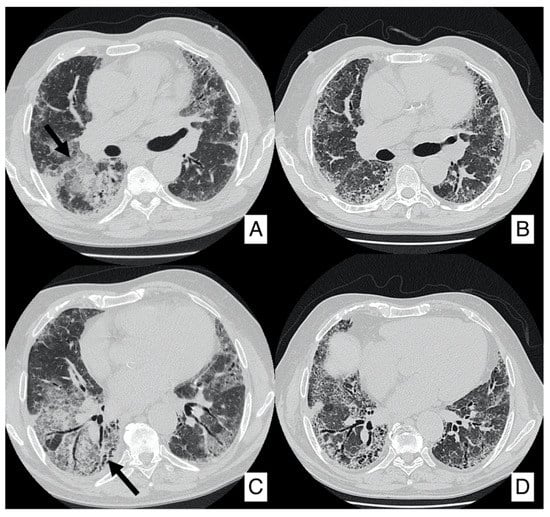

4.2. Acute Exacerbation